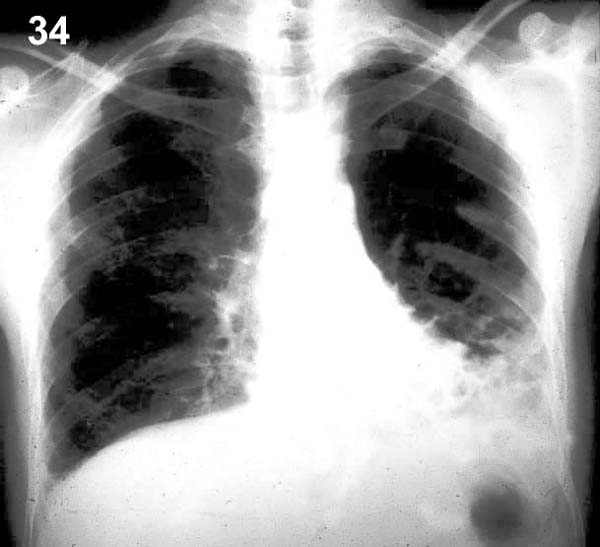

ESQUEMA 34 Comentario placa 34 En la base izquierda y área vecina al borde derecho del corazón hay sombras irregulares dentro de las cuales se distingue con dificultad algunas imágenes areolares mal definidas. Si bien esto permite plantear la sospecha de bronquiectasias su confirmación necesita de una TAC, que es mucho mas sensible para detectar estas alteraciones, como puede apreciarse en la placa que sigue.